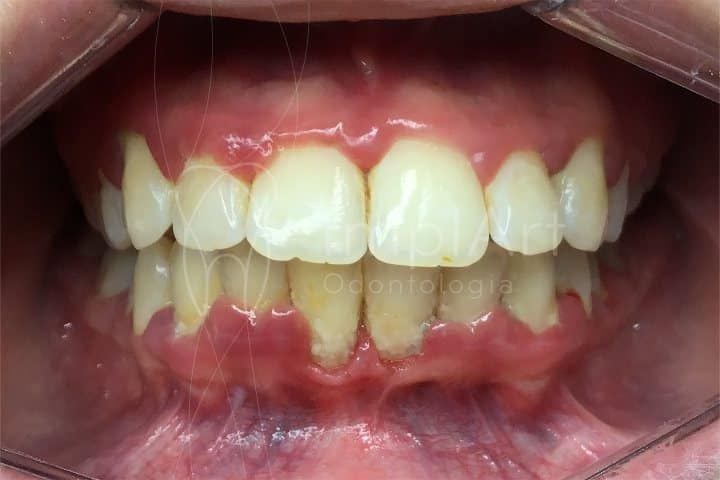

A gengivite crônica é a inflamação da gengiva que, se não tratada, pode evoluir. Ela acontece pelo acúmulo de placa bacteriana. Isso causa vermelhidão, inchaço e até sangramento ao escovar os dentes. Ignorar pode levar a problemas mais sérios, como a periodontite, que afeta os ossos que sustentam os dentes.

A gengivite crônica pode parecer uma coisa pequena, mas se não for tratada, ela pode se agravar e trazer outros problemas. É aquela inflamação persistente que deixa a gengiva inchada e às vezes sangrando. O principal culpado? Acúmulo de placa bacteriana. Pois é, aquela sujeirinha que não sai com uma escovação básica. Precisamos ser mais eficientes na limpeza diária.

Sabe quando a gengiva fica inchada, vermelha e sangra fácil? Se isso já virou rotina, é sinal de gengivite crônica. E olha, ignorar isso só piora o quadro. Muita gente acha que é normal, mas não é. Se você não cuidar, a inflamação pode avançar e virar algo mais sério, como periodontite. Essa é a fase em que o osso que segura seus dentes começa a ser afetado. Ninguém quer chegar nesse ponto, né?

Para não agravar a gengivite crônica, evite algumas coisas que parecem inofensivas. Usar escovas de dente com cerdas muito duras é um erro clássico. Elas machucam a gengiva, piorando a inflamação e o sangramento. Outro ponto é o fio dental. Se você pula essa etapa, a sujeira e as bactérias se acumulam, alimentando o problema. E cuidado com cremes dentais muito abrasivos ou com ingredientes que podem irritar sua gengiva sensível. Leitura atenta do rótulo ajuda.

A gengivite crônica se caracteriza por uma inflamação persistente na gengiva, que fica vermelha, inchada e pode até sangrar com facilidade. Muitas vezes, a causa é o acúmulo de placa bacteriana que não foi removida corretamente com a escovação e o fio dental. Quando ela se torna crônica, os cuidados caseiros podem não ser suficientes para reverter o quadro, e a ajuda profissional se torna indispensável.

| Quando a Ajuda Profissional é Essencial | Sangramento persistente, inchaço acentuado, dor forte, mau hálito crônico, retração geng |